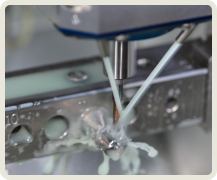

치아 제작시 국내 최고 수준의 장비를 보유한

디지털 치과 전문 기공소와 협업합니다.

이로운 치과는 간단하고 정확하며 안전한 치료를 위한 디지털 진료 방식을 지향합니다.

이 모든 술식, 장비, 소프트웨어 노하우가 집약된

이로운치과의 디지털 임플란트